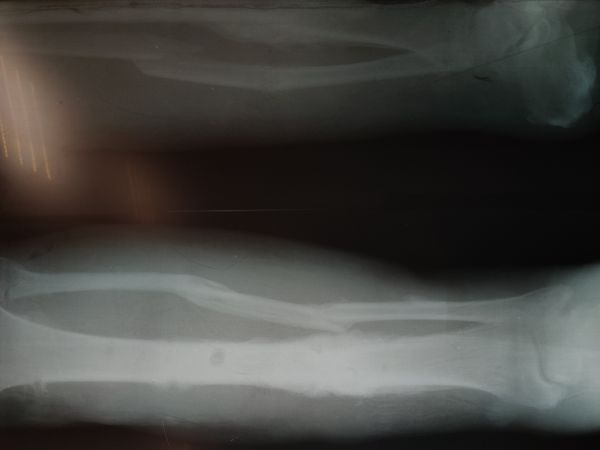

13 апреля 2021 года ему удалили часть большеберцовой кости, устранили деформацию малоберцовой кости и зафиксировали кости левой голени и стопы с помощью аппарата Илизарова. На поражённый участок пересадили свободный расщеплённый лоскут кожи пациента.

Течение раннего послеоперационного периода протекал без осложнений. Контрольная рентгенограмма показала сращение костей правой стопы, поэтому 12 марта сняли аппарат наружной фиксации.